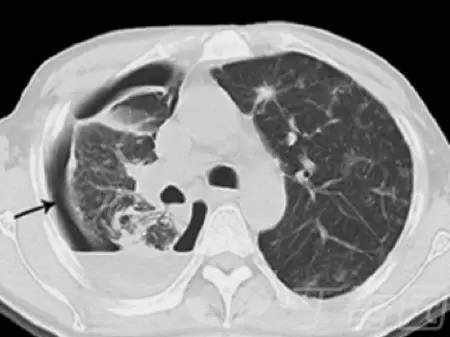

肝癌肺转移:多为血行转移,但部分影像表现有些特别,其表现并不是圆形或类圆形,边缘光整清楚,无分叶,而表现为病变边缘模糊(下图)。

肝癌细胞经由肺动脉血行转移为最常见的转移途径,肝癌组织侵入肝内静脉,形成小的癌栓,癌细胞再经肝静脉与下腔静脉入肺循环,最终造成肺小动脉细小分支栓塞,致肝癌肺转移。